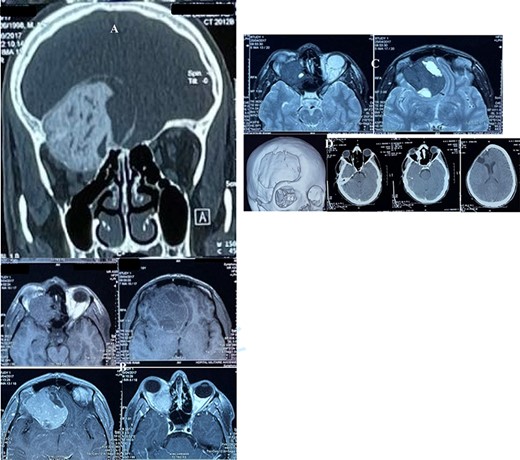

(A) CT scan, bone window, coronal reconstruction, showing well-defined ground glass lesion lying on the orbital roof invading the orbit and above the roof. (B) T1 weighted MRI images showing an expansile, heterogeneous and cystic lesion involving the orbital roof and invading the orbit below and the cranium above, with an enhancing after injection. (C) T2 weighted MRI images: the tumor is of a low intensity, whereas the cystic parts is hyperintense. (D) Postoperative CT scan, showing successful resection of the majority of the lesion.

The cerebral CT scan revealed a large heterogeneous mass with ground glass appearance, which lies in orbit extending to the roof of the right orbit and above the roof, associated with significant bony erosion (Fig. 1A). The lesion was reported radiologically as consistent with skull-base meningioma and less likely ossifying fibroma. On magnetic resonance imaging (MRI), the lesion was delineated more in detail (Fig. 1B–C).

He underwent surgery 3 days later, for the removal of the tumor with resection of the involved frontal bone. The tumor was exposed, grayish and cartilaginous in consistency, and we performed a subtotal removal, the debulking by piecemeal resection. The postoperative period was unremarkable, and the patient was discharged 8 days after surgery (Fig. 1D). The cranioplasty was done successfully a year after his surgical procedure with a good outcome. The sample was sent to the histopathology for analysis and confirmed the lesion to be an ossifying fibroma with fibrous dysplasia and irregularly shaped bony trabeculae embedded within a moderately cellular fibrous stroma (Fig. 2).